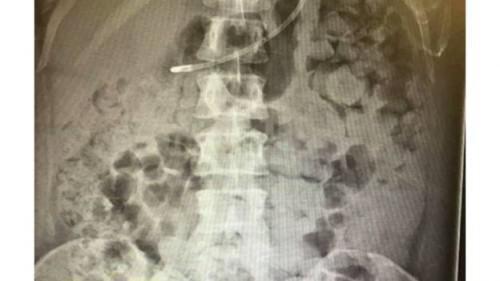

Από την πλευρά του, οι γιατροί του δεύτερου νοσοκομείου κάνουν ό,τι μπορούν για να επαναφέρουν τη λειτουργία του εντέρου της γυναίκας, ενώ εκφράζουν φόβους ότι αυτό θα μπορούσε να υποστεί διάτρηση ανά πάσα στιγμή με θανατηφόρες συνέπειες. Ο φίλος της κοπέλας έδωσε στα media μία πρόσφατη ακτινογραφία από την περιοχή της κοιλιάς της ασθενούς για να γίνει κατανοητό το τι ακριβώς συμβαίνει στο σώμα της και το πώς αυτό έχει επηρεάσει ολόκληρη τη ζωή της.

Από τότε η Γέομαν έχει υποβληθεί σε δύο ακόμα χειρουργεία, ενώ εδώ και 15 εβδομάδες έχει καταστεί αδύνατον να αφοδεύσει, το σώμα της συνεχώς γεμίζει με κόπρανα και η εξαιρετικά δυσάρεστη αυτή κατάσταση εμποδίζει την αναπνοή, τη χώνεψη, ακόμη και την παραμικρή κίνηση της 34χρονης.